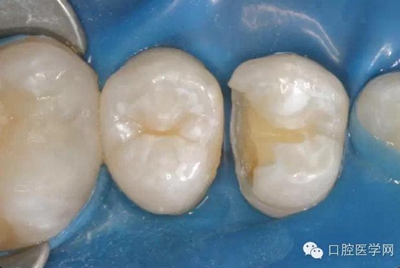

在根管治療之前我們要做麻醉,所以整個(gè)治療的過程是不疼的。治療過程中要使用橡皮障,只露出要治療的牙齒,口腔其他部分都在橡皮障之下,可以隔開唾液,因?yàn)橥僖豪镆彩怯屑?xì)菌的,如果一邊清理,一遍有唾液流到根管內(nèi)部,那么就無法做到完全無菌。同時(shí),有橡皮障的隔絕作用,可以防止治療器械掉到嗓子里,這一點(diǎn)非常重要。